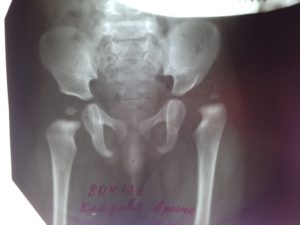

Рентгенограмма тазобедренного сустава ребёнка в норме и при дисплазии

Рентгенография тазобедренных суставов до и после операции по поводу дисплазии ТБС

В норме на снимке врач визуализирует головку бедренной кости, которая находится в специальной выемке – вертлужной впадине.

Головка бедра в центре прикрепляется круглой связкой к вертлужной впадине и удерживается капсулой. Вверху головке не даёт сместиться хрящевая пластина – лимбус. Конструкция сустава поддерживается мышцами бедра.

При дисплазии тазобедренного сустава наблюдается задержка развития точек окостенения. При этом ядра окостенения отличаются меньшей величиной и замедленным ростом. На рентгенограмме при подвывихе или вывихе визуализируют вертикальное и латеральное смещение ядер окостенения. У детей в норме точки окостенения у девочек появляются в 4 месяца, а у мальчиков – в 6-месячном возрасте.

На рентгенограмме у грудничка большая часть тканей сустава не видна, потому что состоит из хрящевой ткани. Поэтому для облегчения расшифровки применяют схему Хильгенрейнера. Она получила практическое применение благодаря достоверности интерпретации снимка.

Оценка рентгенологических данных по схеме Хильгенрейнера